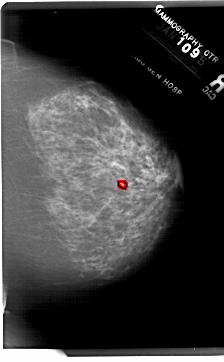

FILE: A_1919_1.RIGHT_CC.OVERLAY

TOTAL_ABNORMALITIES 1

ABNORMALITY 1

LESION_TYPE CALCIFICATION TYPE PLEOMORPHIC DISTRIBUTION CLUSTERED

ASSESSMENT 4

SUBTLETY 2

PATHOLOGY BENIGN

TOTAL_OUTLINES 1

BOUNDARY